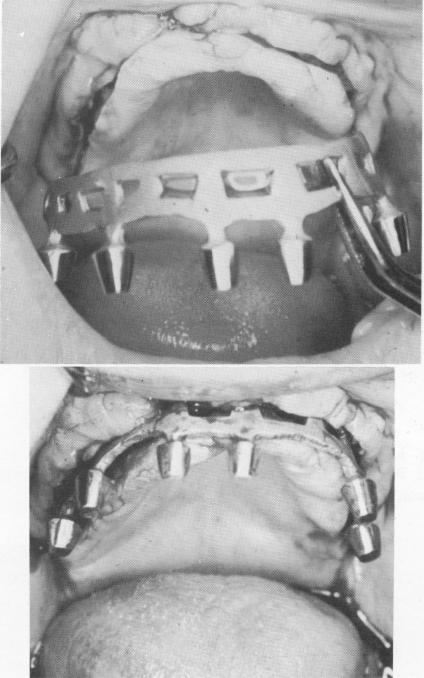

A specially prepared tray was made and an elastic impression taken of the ridge area with the continuous groove (Fig. 11-169). The master stone mode] was poured into the impression. The shallow groove in the separated hardened stone model was deepened to the various depths indicated by Panorex studies of the entire jaw (Fig. 11-170). A cobalt-chrome casting was made. Like individual blades, it was wedge-shaped.

During the following visit, the tissue was once again incised and reflected, and the continuous blade

was placed inside the original groove (Fig. 11-171). It was then tapped deeper with a plastic-headed mallet and inserting instrument until its shoulder was buried (Fig. 11-172). The site was closed with interrupted sutures (Fig. 11-173), and a prefabricated

Fig. 11-171. A one-piece continuous blade was inserted into the groove. (From Linkow, L. I., and Weiss, J. L.: The endosseous blade: a progress report, Prom. Dent., No. 5, 1969.)

Fig. 11-172. The blade was tapped deeper until its shoulder was slightly below the alveolar crest.

3 One piece continuous blade inserted into groove in upper dental arch

4 Dental blade tapped until its shoulder is little below alveolar crest